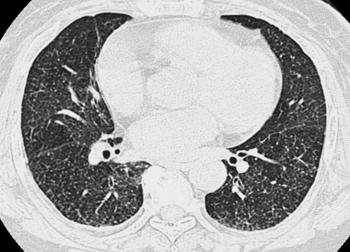

画像診断 41巻2号 (21年1月) ニューモシスチス肺炎(PCP)とサイトメガロウイルス肺炎(CMVP)はHRCT上,いずれも広範なすりガラス影が高頻度であるが,前者ではコンソリデーションや結節の頻度は低いのに対して,後者ではいずれも少なからずみニューモシスチス肺炎の新展開 ニューモシスチス肺炎(以下、pcp)は、aidsなど高度の免疫低下者に合併する重い 日和見肺炎として知られて来ましたが、その診断・治療方法は大体確立し、問題として は一段落といった様相です。画像 (1) 臨床検査 (0) 表 (0) 肺胞気動脈血酸素分圧較差 ニューモシスチス肺炎 Pneumocystis jiroveciiは免疫抑制患者,特にヒト免疫不全ウイルス(HIV)感染患者およびコルチコステロイドの全身投与を受けている患者における肺炎の一般的な起因菌である。症状と

逆に、aids患者の気胸を見たときには、ニューモシスチス肺炎を疑う。 亜急性〜慢性(28週)の経過で発症。一方でnonhivは急性。 aids患者の60%がpcp発症で発見。 nonhivpcpは死亡率3550%。hivpcpは死亡率10%。 症例 hiv陽性患者のpcp画像所見2症例 Kerley line,hilar haze, 気管支血管周囲肥厚 :左心不全 Tram line:気管支拡張症,気管支炎,びまん性汎細気管支炎 (画像引用元 不明) 47 ニューモシスチス肺炎のスリガラス影 48 ニューモシスチス肺炎のスリガラス影 (XPで見える場合) 49>画像所見 : 両下肺野優位で微細な網状影とすりガラス影が広がっている。 >診断 : ニューモシスチス肺炎(旧 カリニ肺炎) >解説 : 広範なすりガラス影を示す代表的な疾患としては、 ニューモシスチス肺炎とサイトメガロウイルス肺炎があげられる。

ニューモシスチス肺炎 カリニ肺炎 Pcp のct画像診断のポイント